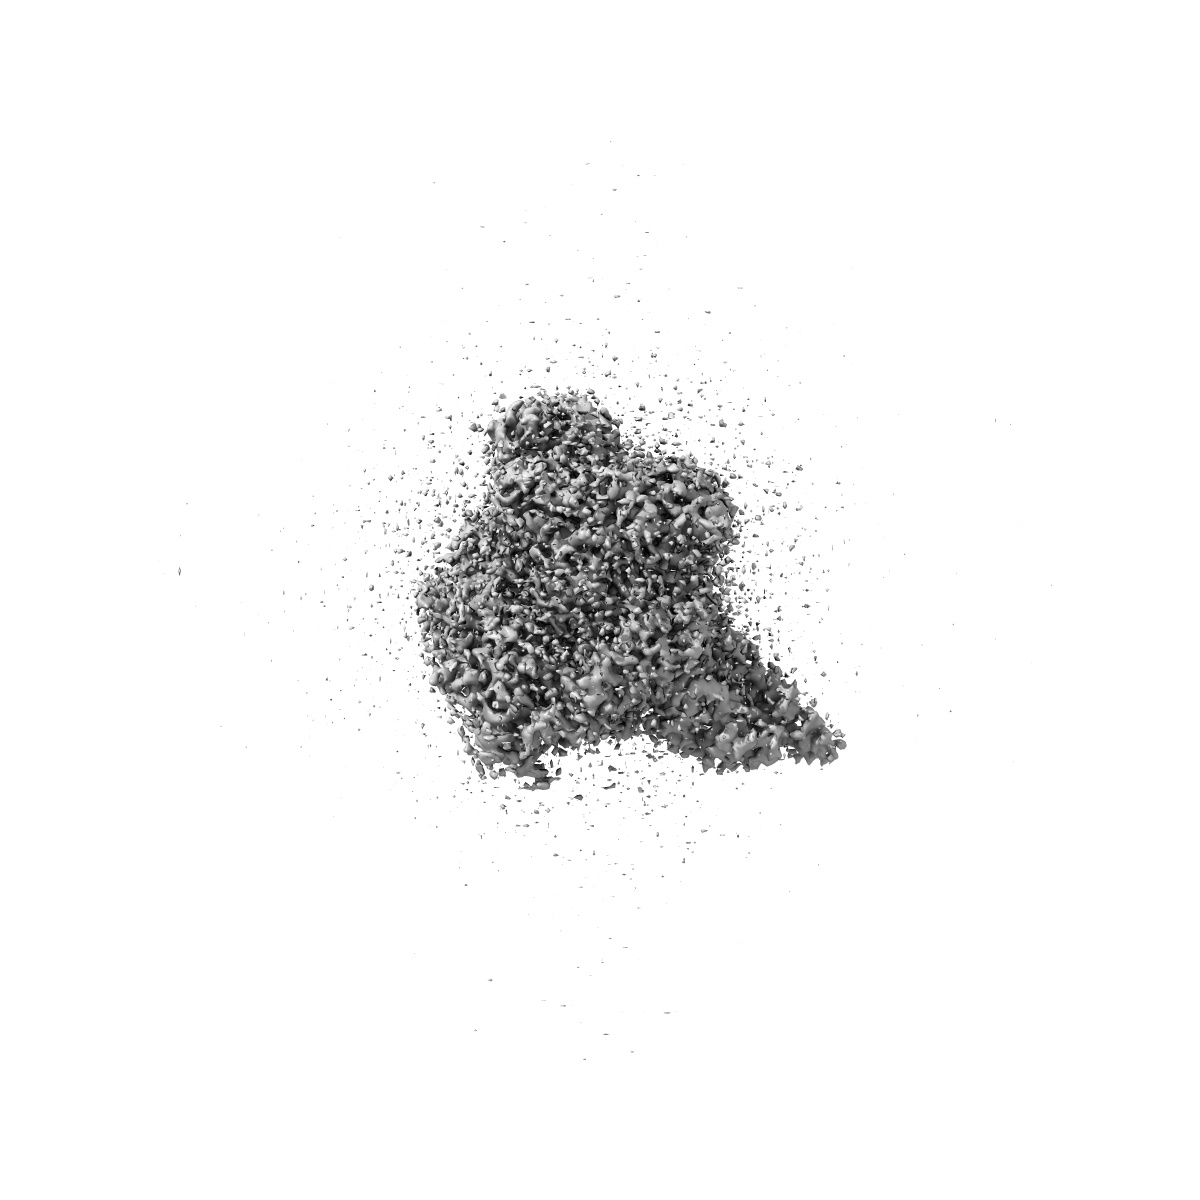

Cryo-EM structure of cancer-specific PI3Kalpha mutant H1047R in complex with BYL-719

Single-particle2.73 Å

Sample: Human PI3Kalpha mutant H1047R in complex with BYL-719